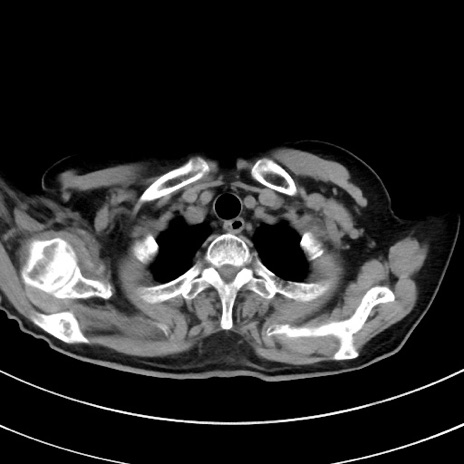

冠状断像